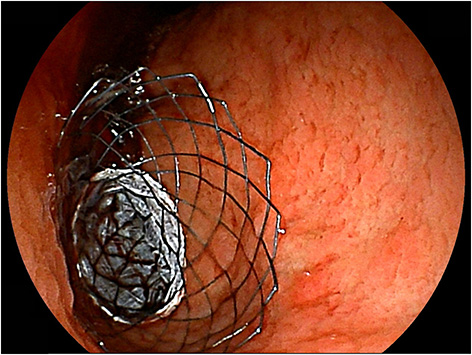

The CSEMS was developed with the expectation of reducing the risk of stent blockage due to tumor ingrowth and hyperplasia (Figure 5). Stent wires are not embedded into the gastrointestinal wall because of the presence of a covering membrane, which may lead to a higher risk of stent migration. Although a recent meta-analysis from seven randomized controlled trials and nine observational studies (72) also showed CSEMS was associated with a higher rate of migration, CSEMS eventually performed better with prolonged stent survival compared with uncovered SEMS (USEMS) (HR:0.68, 95% CI: 0.48–0.96, P = 0.03) (72). However, a subsequently published large-scale RCT comparing CSEMS and USEMS (73) showed conflicting results, with better overall stent patency in USEMS (35.2 vs. 23.4%, P = 0.01). Nevertheless, the risk of stent migration remains high with CSEMS, and stent designs with various anti-migration properties have been developed and evaluated. An RCT comparing CSEMS and USEMS in patients with gastric cancer (74) was conducted. The CSEMS used in this study was designed to have a reduced radial force and indentation in the central part of the SEMS, with an uncovered flared portion at both ends. Despite no statistically significant difference in migration rate between both groups, the migration rate was rather high at 9.8% in CSEMS (74). A study with the use of partially-covered “big cup” SEMS was prematurely terminated because proximal migration occurred in three out of six patients (75). Choi et al. evaluated patients with GOO who were treated with a newly designed, partially covered SEMS that had star-shaped wing flaps at the proximal end to reduce distal stent migration (76). In this study, proximal migration occurred in 11.1%, with no distal migration (76). Therefore, there is a need to develop more efficient antimigration systems.

Figure 5

Placement of covered SEMS. A patient with antral gastric cancer was treated with partially-covered SEMS.